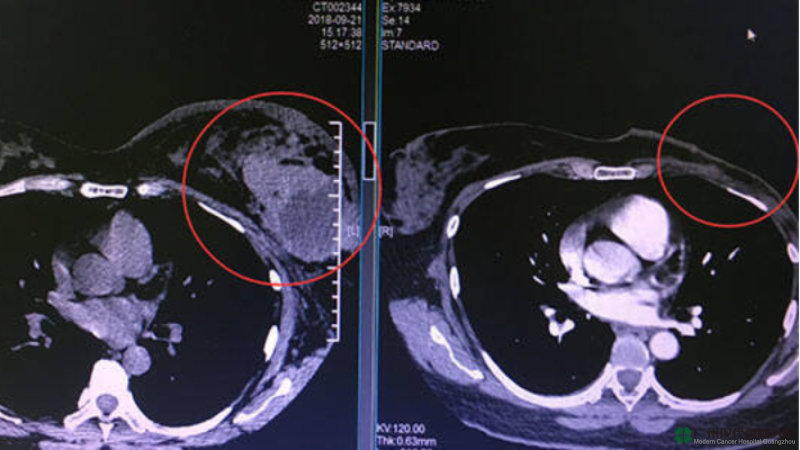

(Ảnh bên trái là hình ảnh khi Saidah nhập viện vào tháng 9 năm 2018, bên phải là hình ảnh vào tháng 6 năm 2019, có thể thấy khối u đã hoàn toàn hoại tử. )

Vào ngày 20 tháng 9 năm 2018, Saidah lần đầu đến Bệnh viện Ung thư Hiện đại Quảng Châu St.Stamford, khi đó kích thước khối u của chị là 12cm, khi nhập viện, đầu vú chị đau đến mức chị không thể nghĩ đến vấn đề gì. Sau đó đội ngũ y tế MDT của bệnh viện đã lập một phương án điều trị xâm lấn tối thiểu toàn diện là "liệu pháp can thiệp + liệu pháp áp lạnh" dựa theo bệnh tình của Saidah, tính đến nay thì chị đã trải qua 8 lần can thiệp + 2 lần áp lạnh. Sau khi được điều trị can thiệp lần 2, khối u đã thu nhỏ còn 7cm.